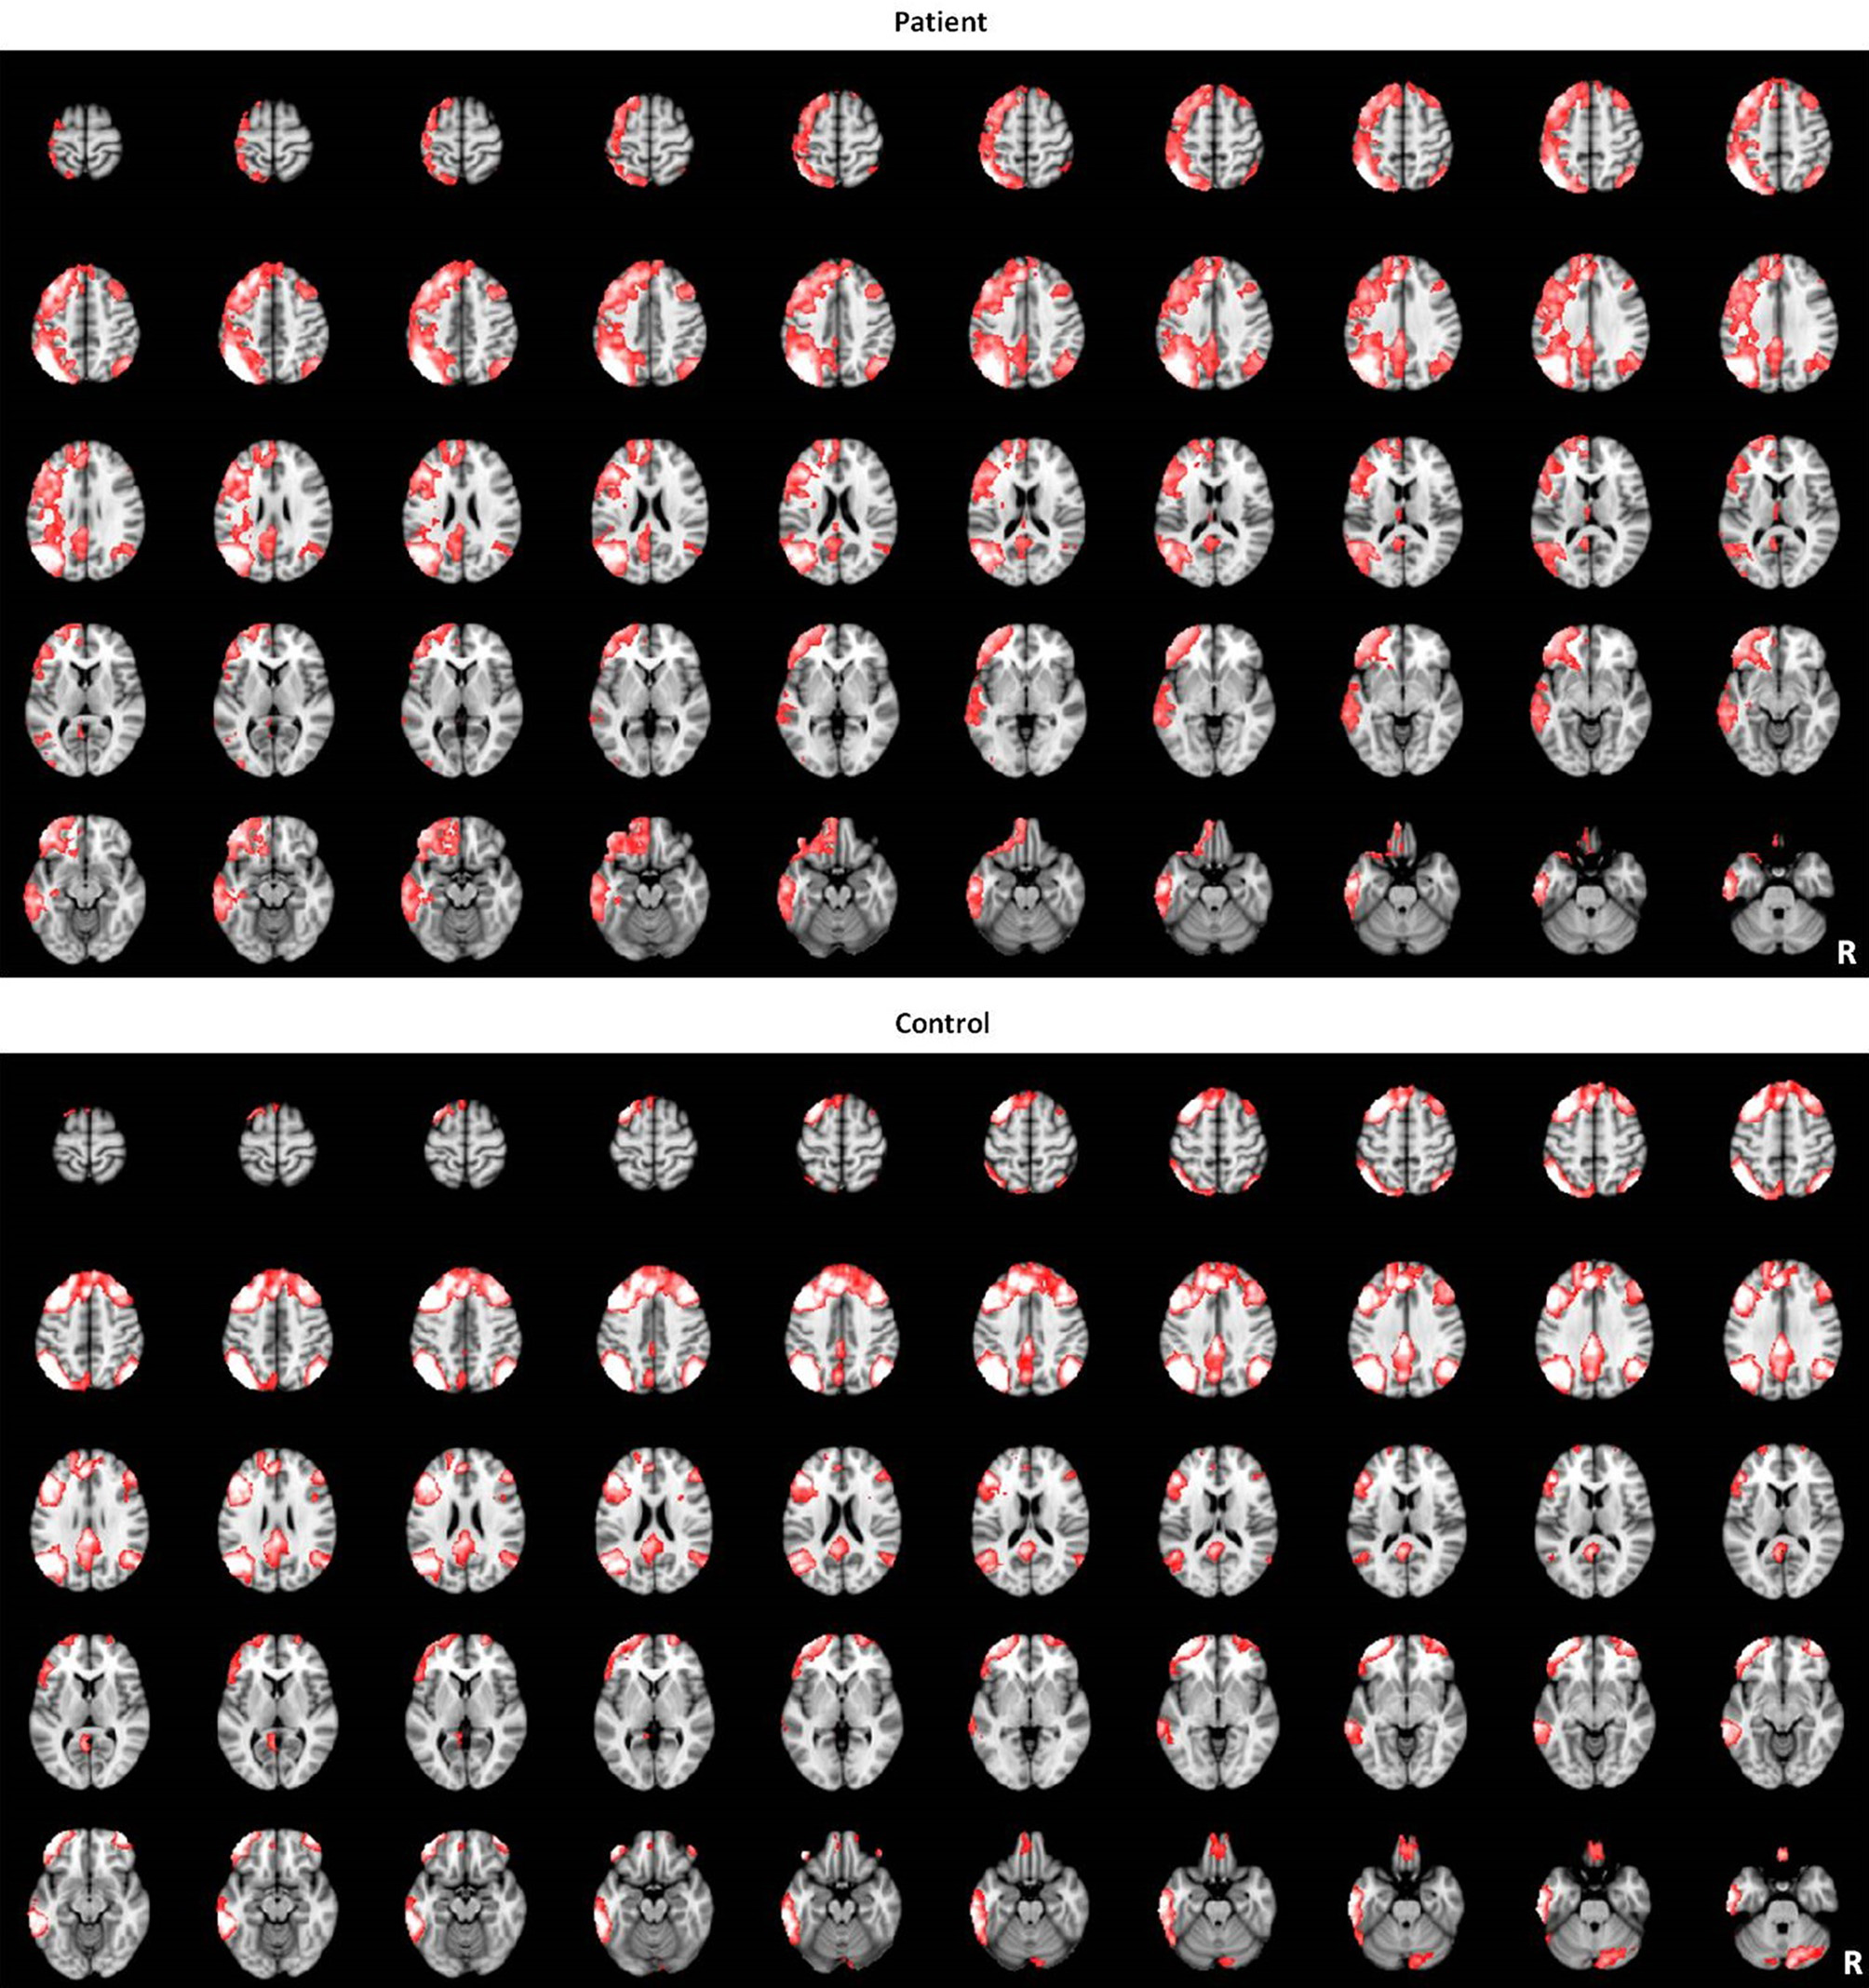

Figure 3

The LFPN identified by group-level ICA in patients and controls groups.

Results from ICA analysis

The LFPN that we obtained from our cohort of subjects includes the bilateral parietal cortex, bilateral frontal cortex, medial frontal cortex and posterior cingulate cortex (Figure 1). We obtained 20 spatial and temporal components from the ICA analysis and noted that the results from previous ICA analyses support the selection of the LFPN (Smith et al., 2009; Biswal et al., 2010). The group-level ICA was performed separately in patients and controls (Figure 3).